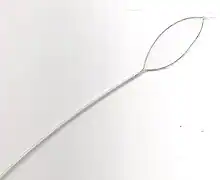

Other tools may be used to remove food boluses. The Roth Net is a mesh net that can be inserted through the endoscope, and opened and closed from the outside; it can be used to retrieve pieces of obstructed food. Snares, which are normally used to remove polyps can be used to macerate the food causing the obstruction. Dormia baskets, which are metal baskets used to remove stones from the common bile duct in a procedure known as endoscopic retrograde cholangiopancreatography, can be opened and closed from the outside in a similar manner to macerate food and facilitate removal. Forceps used for biopsies can also be employed in a similar manner.[24]